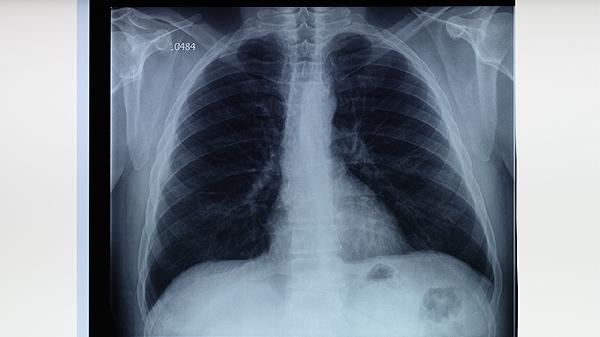

3、肺结核的病因及预防。肺结核主要通过空气传播,与感染者密切接触、免疫力低下、营养不良等因素增加患病风险。预防措施包括接种卡介苗、避免与患者密切接触、保持良好卫生习惯、增强免疫力等。高危人群应定期进行结核菌素试验或胸部X线检查,早发现早治疗。

婴幼儿结核病可通过结核菌素试验、胸部X线检查、痰涂片镜检、γ-干扰素释放试验等方式检查。 1、结核菌素试验: 通...